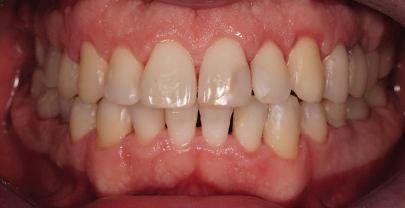

Пациентът постъпи в клиниката с молба за тотална рехабилитация на усмивката. Той не харесваше централ ните си резци, които според него бяха твърде къси и квадратни. Имаше раз стояние от медиално и дистално на латералните му резци. Друго сериоз но оплакване бе свързано с металоке рамичната корона на зъб 12, която бе жълтеникава и неестетична, като цяло не харесваше вида на венците си и както самият той се изразяваше, „вижда се прекалено много от венците при усмивка“.

След диагностиката бяха направени екстра- и интраорални снимки, както и рентгенографии; професионалното почистване бе от изключителна важ ност, бяха дадени и инструкции за лич на орална хигиена. Бе направено интра орално сканиране с Medit i500. Цялата тази информация бе използ вана в приложението Smilecloud за 2D биометричен дизайн. В приложението са налични естест вени форми на зъбите и щом бяха под брани зъби и бе направен дизайн

библиотеката на Exocad. Струва си да се отбележи, че 2D дизайнът от Smile Cloud бе спазен до последния детайл в Exocad smile creator с цел да се създаде 3D obj файл със зъбните форми. След като естетичният дизайн бе готов в model creator модула на Exocad, адитивен 3D мок-ъп модел бе експорти ран и принтиран от принтер Formlabs 3. Моделът бе използван за направата на силиконов водач, за да се изготви мо тивационен мок-ъп в устата на паци ента и да се оценят естетичните па раметри. След като пациентът одобри вида на усмивката си, мок-ъпът бе използван за финализиране дизайна на усмивка та. Мок-ъпът бе използван също така като водач по време на мекотъканна та хирургия, както и при препарация на зъбите.

Препарираните зъби бяха импорти рани в Exocad и насложени върху ес тествените форми от биометричния дизайн, като така стана ясно дали зъ бите са били препарирани коректно. По този начин зъболекарят и зъботехни кът работят в една и съща екосистема и резултатът е оптимален. С короната се справихме чрез диги тална редукция на циркония в Exocad, като по този начин на практика създа дохме циркониево кепе, след което про изведохме фасета от IPS Empress Cad Multi. Кепето от Katana Zirconia на зъб 12 с букално послойно нанесена керами ка бе фрезовано (послойното нанасяне бе направено, за да се подобри връзката и да се осигури адхезивно циментиране на фасетата към циркониевото кепе, както и за да се напасне цветът към този на съседните зъби). При първото сканиране регистрирах ме цялата горна зъбна дъга, така че, ко гато се наложи да сканираме повторно, бе изтрит и сканиран наново само зъб 12, тъй като венците не бяха отдръп нати при второто сканиране.

Една седмица след препарацията на зъбите и циментирането на цирко ниевото кепе бяха изработени 12 IPS Empress Cad Multi фасети. Макро- и микротекстурата на фасе тите бяха направени на ръка, след кое то бяха нанесени 3D характеризации с боички, а полирането отново бе напра вено ръчно, за да им се придаде естест вен и естетичен вид. Предизвикателството тук беше короната да има същите оптични характеристики като тези на остана лите зъби при естествена светлина, през поляризационен и флуоресцентен филтър. 3D принтерът бе Fromlabs, софтуерът за фрезоване – Mill Box, а фрез апаратът –imes icore CORiTEC 350i. В крайна сметка постигнахме ес тествен вид на усмивката с натурал на зъбна морфология при изцяло диги тален протокол, при който дизайнът бе направен първоначално и през всич ки етапи на лечението се придържахме към него до самия край Излишно е да отбелязваме, че всички сме удовлетворени от постигнатото! Преди След Победител в категория „Клиничен случай с изцяло дигитален протокол“ в конкурса „Усмивка на годината 2022“